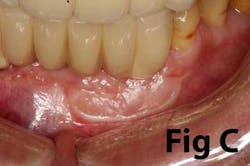

Case No. 2

There is an abundance of literature showing increased gingival inflammation around natural dentition (exacerbated when a fixed restoration is present) when there is less than 2 mm AG. (Figs. 8, 9: post grafting) There is an abundance of literature showing increased incidence of peri-implant mucositis when there is inadequate attached tissue — a weaker connective tissue adhesion and lack of Sharpey’s fibers make the peri-implant tissue even more susceptible to bacterial challenge. (1-6, 8, 10) And as periodontitis is always preceded by gingivitis, peri-implantitis will be preceded by peri-implant mucositis. If we can decrease the incidence of peri-implant mucositis by providing a better and more resilient tissue phenotype, we can lower the incidence of peri-implantitis.The FGG procedure is indicated in cases of implant therapy where this is less than 2 mm of attached tissue present. Sometimes, a FGG is preferred over CTG because: (1) the FGG results in greater gain of attached tissue, (2) the FGG alleviates frenum/muscular pull whereas the connective tissue may increase muscular tension after the flap is coronally advanced, and (3) creeping attachment is often a positive byproduct of the FGG procedure.